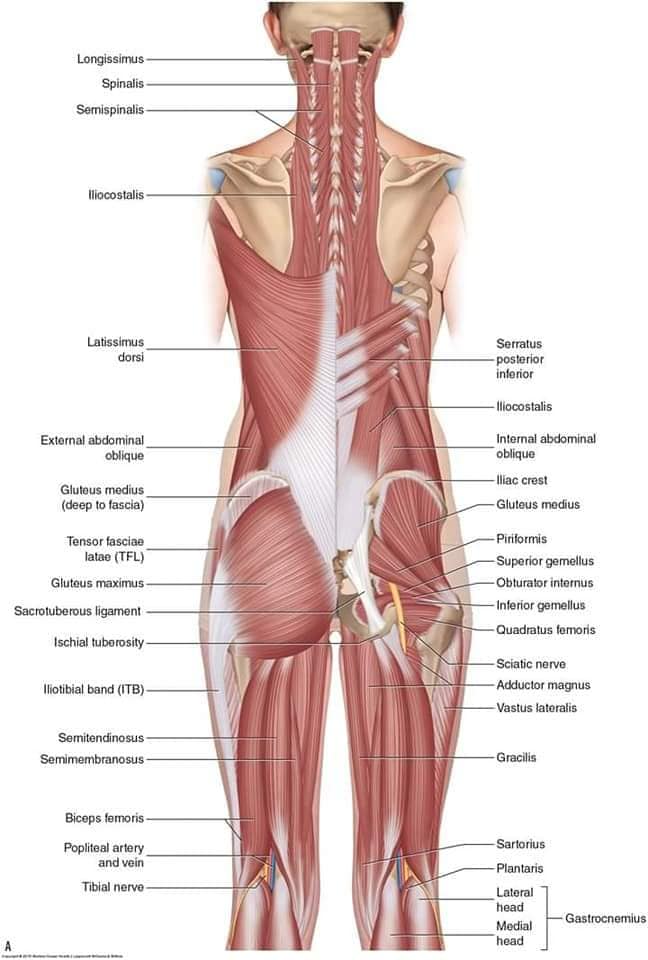

М'язова система людини є однією з основних систем організму, що відповідає за рухи, підтримання пози та стабільність. Вона складається з понад 600 м'язів, які можна класифікувати на скелетні, гладкі та серцеві м'язи. Скелетні м'язи, які є об'єктом нашого детального розгляду, дозволяють контролювати навколишній світ і виконувати різноманітні рухи. Особливу увагу в нашій статті буде приділено шейним і спинним м'язам, оскільки ці групи м'язів мають критичне значення для підтримання правильного постава та функціонування хребта.

Спинні м'язи

Спинні м'язи виконують функції підтримки хребта, а також дозволяють здійснювати рухи тулуба.

Поверхневі спинні м'язи

М'язи, що піднімають лопатку: Трапецієподібний м'яз: великий м'яз, що покриває верхню частину спини. Його функція - підтримка і рух лопаток, а також забезпечення стабільності хребта.

М'язи, що ведуть лопатку до хребта: Широкий м'яз спини: великий м'яз, що розташований в нижній частині спини. Він відповідає за рухи плечей і лопаток, а також за розширення верхньої частини тулуба.

Глибинні спинні м'язи

М'язи, що забезпечують стабільність хребта: М'язи, що розташовані між хребцями: включають мускулатуру, яка забезпечує стабільність і підтримку хребта, а також дозволяє здійснювати рухи хребта.

М'язи, що здійснюють ротацію та нахили

М'язи, що забезпечують ротацію хребта: Ротаційні м'язи: допомагають у здійсненні обертальних рухів тулуба, а також у підтримці рівноваги і стабільності хребта.